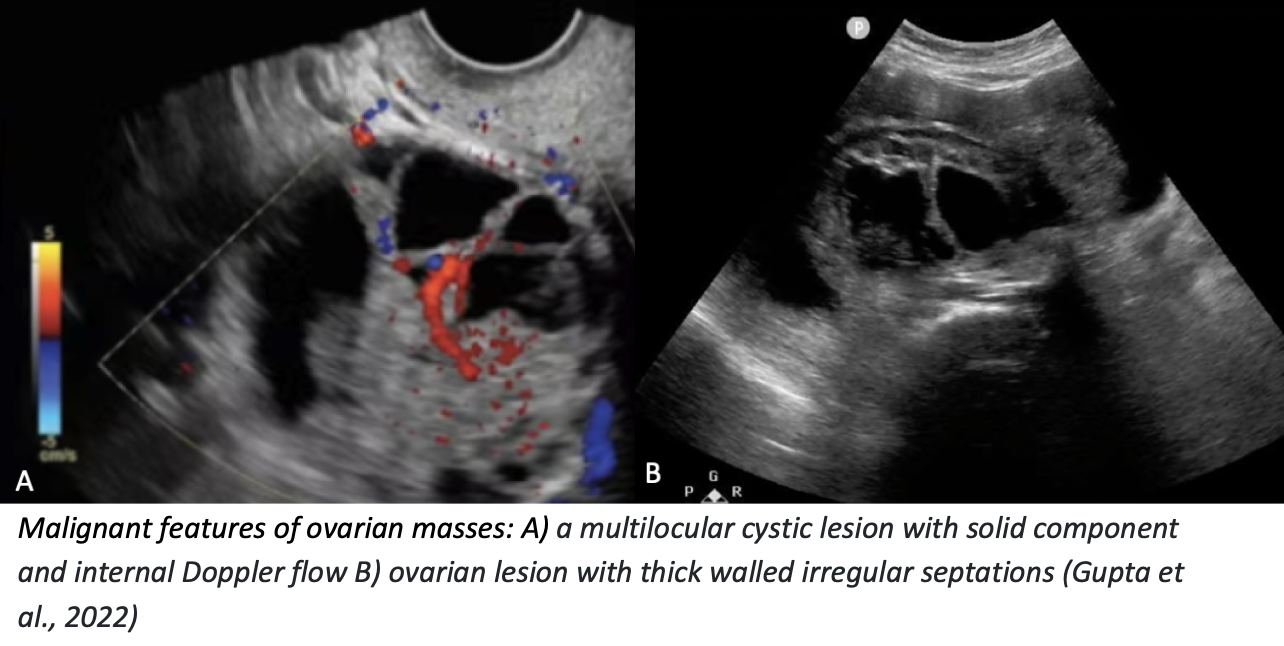

Neoplastic / Malignant Features

PoCUS features

- Thick-walled (> 2–3 mm), irregular septations

- Solid components with vascularity on Doppler

- Papillary projections (especially with flow)

- Ascites or peritoneal implants may be seen

Management / Follow-up

-

Radiology-performed ultrasound ± CT

Gynecology referral

Gupta, A., Kim, K. A., Feldstein, V. A., Peterson, E., Zaloudek, C. J., & Lee, S. I. (2022). Ovarian cancer detection in average-risk women: Classic- versus nonclassic-appearing adnexal lesions at US. Radiology, 305(3), 575–584.